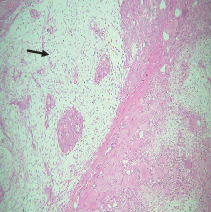

多形性腺瘤(PA)是最常见的唾液腺肿瘤,由于其多样的临床病理特征而面临着独特的挑战。本病例系列的目的是强调详细的组织病理学检查的含义,以指导适当的诊断。本研究回顾了2011年至2023年间在尼泊尔B.P.柯伊拉腊健康科学研究所诊断的10例前列腺癌病例。患者年龄16 ~ 71岁,男女比例1:2.3。多数病变(8例)位于上颚,另有1例位于上唇,1例位于颊黏膜。病变大小1 ~ 3cm2,病程2个月~ 4年。临床上,所有病变均包被良好,无压痛,无溃烂,上覆粘膜正常。组织病理学上,病例包括经典PA、黏液型和细胞型。常见的表现为充满嗜酸性物质的导管结构,蜂群状,浆细胞样细胞和粘液样间质。部分病例可见鳞状分化和沙粒小体。未发现骨性或软骨成分。所有病例均被切除,在至少2年的随访中无复发报告。因此,正确的诊断对于PA的有效管理和长期预后至关重要。

Pleomorphic adenoma (PA), the most common salivary gland tumor, presents unique challenges due to its diverse clinicopathologic features. The objective of this case series is to highlight the implication of detailed histopathological examination to guide appropriate diagnosis. This study reviews 10 cases of PA diagnosed at B.P. Koirala Institute of Health Sciences, Nepal, between 2011 and 2023. Patients ranged from 16 to 71 years, with a male-to-female ratio of 1:2.3. Most lesions (eight cases) were located on the palate, with additional cases, one on the upper lip and one on the cheek mucosa. Lesion sizes ranged from 1 to 3 cm2 and durations from 2 months to 4 years. Clinically, all lesions were well encapsulated, nontender, and nonulcerated and had normal overlying mucosa. Histopathologically, cases included classical PA, myxoid, and cellular types. Common findings were ductal structures filled with eosinophilic material, a "swarm bee" appearance, plasmacytoid cells, and myxoid stroma. Squamous differentiation and psammoma bodies were observed in some cases. No osseous or cartilaginous components were detected. All cases were excised, with no recurrences reported during at least 2 years of follow-up. Hence, proper diagnosis is crucial for effective management and long-term outcomes of PA.